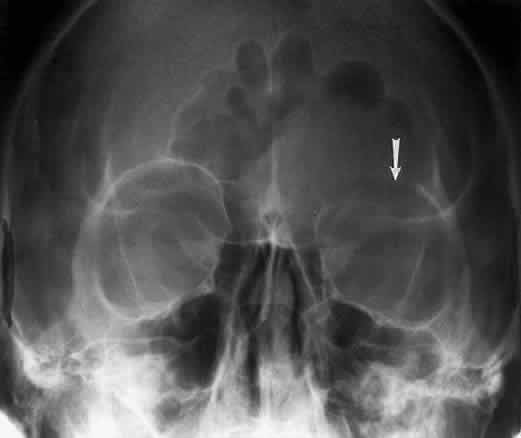

Hyperostosis of the orbital bones may be associated with a variety of disorders. The most common cause is a meningioma of the sphenoid bone (Fig. 14). Fibrous dysplasia, osteoblastic metastatic disease, or Paget's disease can also cause these bony changes.

Fig. 14. Caldwell projection showing an optic nerve sheath meningioma of the left orbit. The increased radiodensity is caused by the calcium content of the meningioma. This patient had exophthalmos and marked reduction in vision.

The optic foramen should measure 6 mm vertically and 5 mm horizontally. Asymmetry greater than 1 mm or a vertical dimension greater than 6.5 mm is considered abnormal.15,27 Ninety-eight percent of patients have optic canals that vary by less than 1 mm.27 Concentric enlargement of the foramen and optic canal can be seen with optic nerve gliomas, meningiomas, neurofibromatosis, and less commonly an aneurysm of the ophthalmic artery (Fig. 16). A decrease in the optic foramen and canal dimension can be seen in fibrous dysplasia, Paget's disease, hyperostosis secondary to a meningioma, or microphthalmos (Fig. 17, Table 1).

Fig. 17. Bilateral optic canal compression from fibrous dysplasia. There is diffuse bone thickening in each orbit. Note small size of optic foramen (arrow).